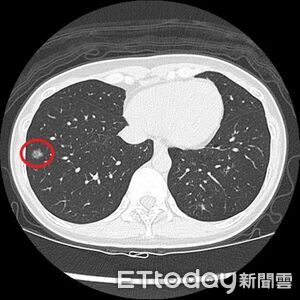

年約40歲的陳小姐過去有抽菸習慣,近2年戒掉,日前身體雖無不適,但符合公費低劑量電腦斷層(LDCT)篩檢條件,決定去檢查,結果在右肺發現一顆約1.2公分的毛玻璃結節,經手術切除後,病理檢查確診為肺癌;醫師說,此案例凸顯即使已戒菸且無症狀,仍可能有早期肺癌,民眾不能輕忽。 《詳全文...》